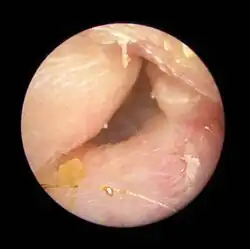

Exostoses in the ear canal, as seen through otoscopy

Surfer's ear is the common name for an exostosis or abnormal bone growth within the ear canal. They are otherwise benign hyperplasias (growths) of the tympanic bone thought to be caused by frequent cold-water exposure.[1] Cases are often asymptomatic.[1] Surfer's ear is not the same as swimmer's ear, although infection can result as a side effect.

Irritation from cold wind and water exposure causes the bone surrounding the ear canal to develop lumps of new bony growth which constrict the ear canal. Where the ear canal is actually blocked by this condition, water and wax can become trapped and give rise to infection. The condition is so named due to its high prevalence among cold water surfers, although it can occur in any water temperature due to the evaporative cooling caused by wind and the presence of water in the ear canal.

The normal ear canal is approximately 7 mm in diameter and has a volume of approximately 0.8 ml (approximately one-sixth of a teaspoon).[5] As the condition progresses, the diameter narrows and can even close completely if untreated, although people generally seek help once the passage has constricted to 0.5–2 mm due to the noticeable hearing impairment. While not necessarily harmful in and of itself, constriction of the ear canal from these growths can trap debris, leading to painful and difficult to treat infections.